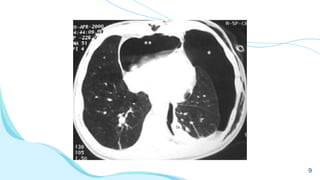

9

ACHADOS

RADIOLÓGI

COS

➔ Diâmetro brônquico aumentado

(sinal do anel de sinete);

➔ Sinal do trilho do trem;

➔ Brônquios visíveis nas periferias

pulmonares;

➔ Brônquios não afilam

progressivamente;

➔ Impactação mucoide;

24

ACHADOS RADIOLÓGI COS ➔ Diâmetro brônquicoaumentado (sinal do anel de sinete); ➔ Sinal do trilho do trem; ➔ Brônquios visíveis nas periferias pulmonares; ➔ Brônquios não afilam progressivamente; ➔ Impactação mucoide; 24